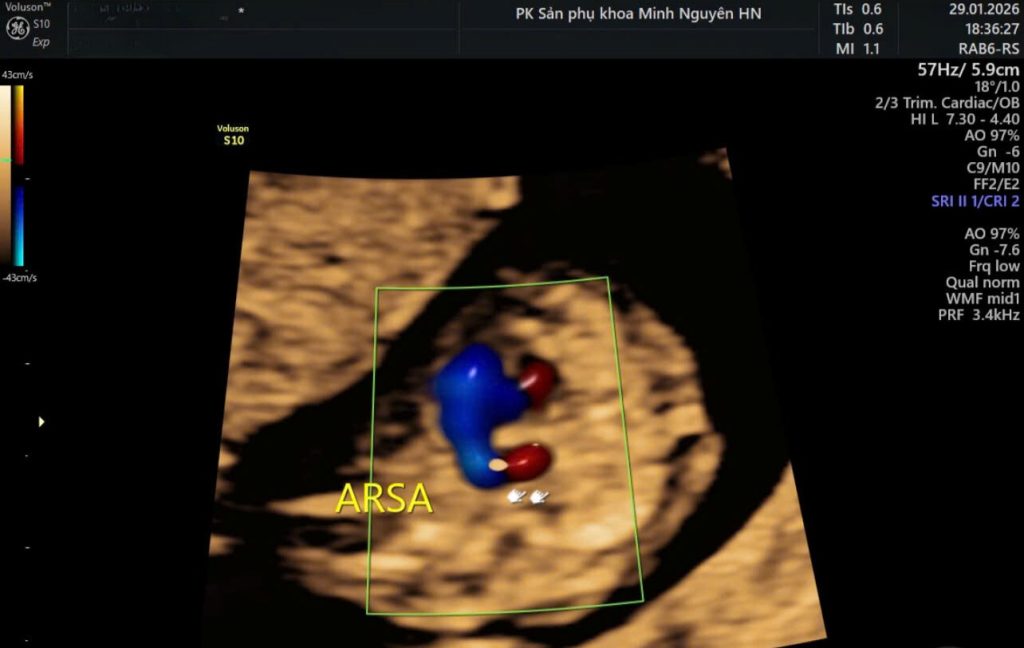

Siêu âm thai phát hiện động mạch dưới đòn phải lạc chỗ như thế nào?

ARSA trên siêu âm thai có thể được phát hiện từ quý I, ở mốc 11–13 tuần, khi khảo sát mặt cắt ba mạch máu và khí quản bằng Doppler màu.

Tuy nhiên ở giai đoạn sớm này, kích thước tim thai còn nhỏ nên việc nhận diện đòi hỏi kinh nghiệm và kỹ thuật cao. Không phải mọi trường hợp đều phát hiện được từ 12 tuần.

Ở mốc hình thái 18 – 22 tuần, việc khảo sát mặt cắt ba mạch máu và khí quản rõ ràng hơn. Doppler màu giúp xác định nhánh mạch đi phía sau khí quản sang phải, là dấu hiệu đặc trưng của ARSA.